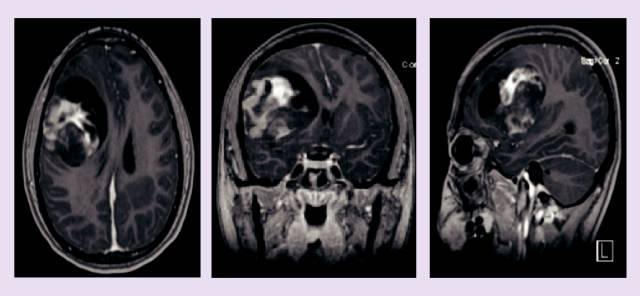

患者在13岁时被诊断为胶质母细胞瘤,在进行手术切除之后,进行了放疗和化疗,但是病情还是进展了。通过MRI 进行了6个月的观察我们可以观察到离散的肿瘤生长,随后,我们开始使用电场疗法进行临床及影像监测7个月,病情稳定。电场疗法起到了预防胶质母细胞瘤复发和抑制其生长的作用,并且在七个月的治疗期间,对13岁的女孩无重大不利影响。我们认为,电场疗法在胶质母细胞瘤的治疗中有潜在价值。

患者手术后开始进行放疗联合替莫唑胺及铂类化疗治疗,在初步诊断后的20个月时,肿瘤复发,出现两个新病灶。随后,她接受了第二诊疗意见(会诊),会诊为她制定了贝伐单抗联合电场治疗的方案。在她手术后的5周,开始接受每两周10 mg/kg贝伐单抗治疗,在使用贝伐单抗六周后,患者开始接受电场治疗。这期间,贝伐单抗持续联合电场治疗,直到病情进展。(13个月)

由于她的病史,她需要每个月接受一次评估和神经系统检查,实验室检查和MRI。治疗过程中的副作用非常小,仅为轻微的头皮刺激和皮肤症状,使用非处方药氢化可的松治疗后缓解。她恢复到正常的生活中。在进行电场治疗的6~7个月,病情稳定。7个月后,MRI显示病情进展,患者停止接受电场治疗,继续贝伐单抗的治疗,并做了美国Foundation medicine基因检测公司的全基因组测序。基于检测结果显示ROS1突变,她开始使用克唑替尼治疗。